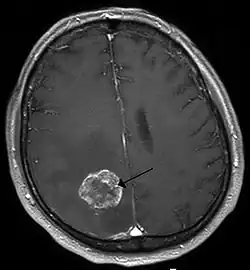

Métastase cérébrale

Une métastase cérébrale est une dissémination de cellules cancéreuses (métastases) dans le tissu cérébral. Cela désigne des tumeurs malignes originant de l'extérieur du cerveau.

Les métastases cérébrales viennent souvent du cancer du poumon, du cancer du sein, du cancer du rein et de mélanome malin[1]. Ce sont les tumeurs les plus fréquentes au niveau du cerveau[2]. Elles peuvent se faire sentir, entre autres, par des maux de tête, des troubles neurologiques, des convulsions et des changements d'attitude. Le traitement et les chances de guérison dépendent de nombreux facteurs, mais les métastases cérébrales ont généralement un pronostic défavorable.